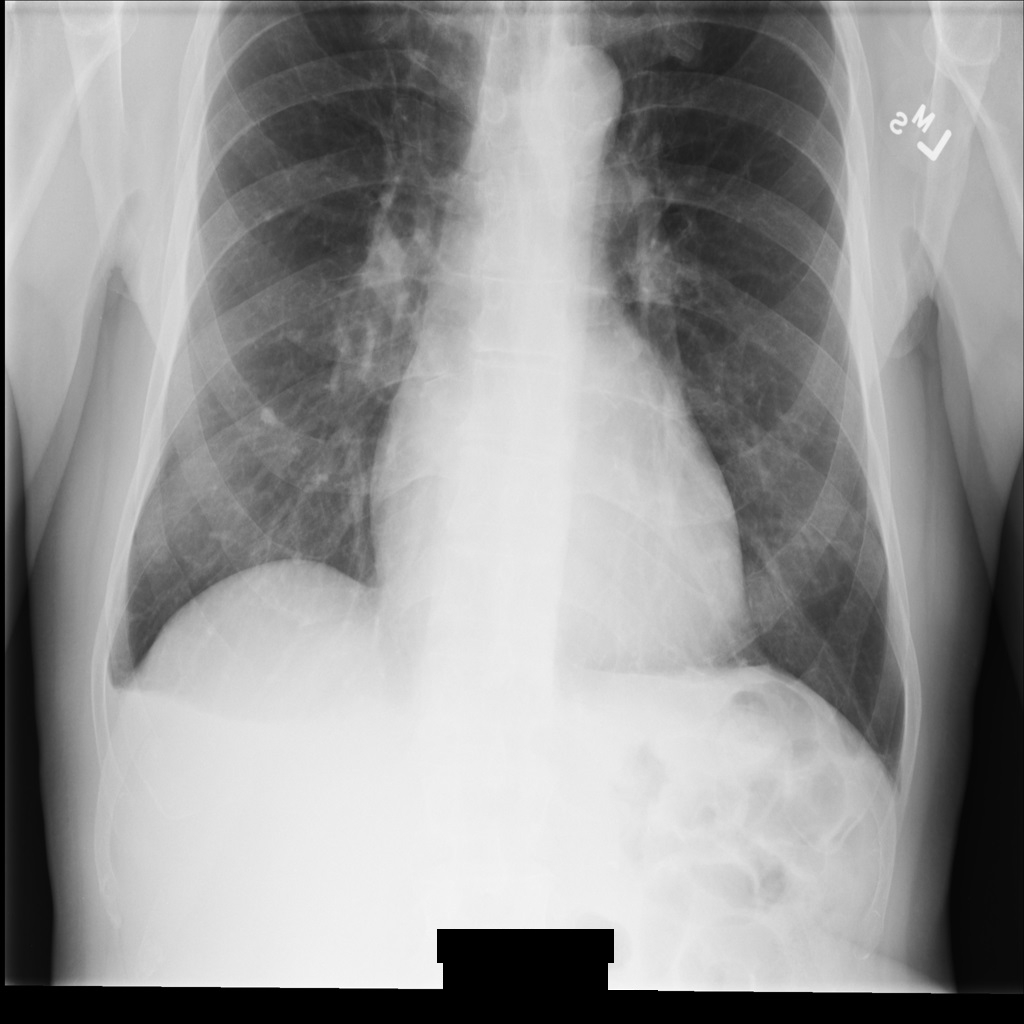

REDACT_ALL_TEXT를 사용하여 이미지를 익명화하면 이미지는 다음과 비슷합니다. 이미지 하단의 번인 텍스트가 모두 수정된 것을 볼 수 있습니다.

REDACT_ALL_TEXT를 사용하여 익명화한 후의 DICOM 인스턴스설명어 정리 옵션을 사용하여 민감한 텍스트 수정